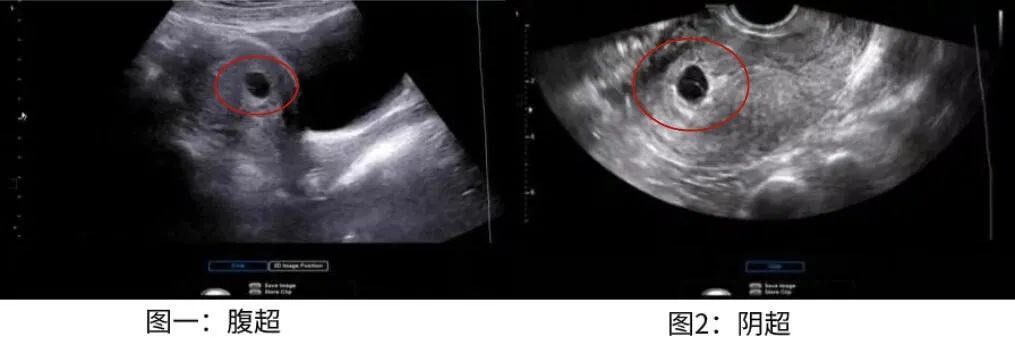

这位妈妈做腹超和阴超检查的不同结果如下图,图1是腹超,图2是阴超,图中椭圆形黑色区域是孕囊,相比之下,明显可见阴超显示的孕囊要比腹部清晰很多。

图源:邦彦医院学习资料